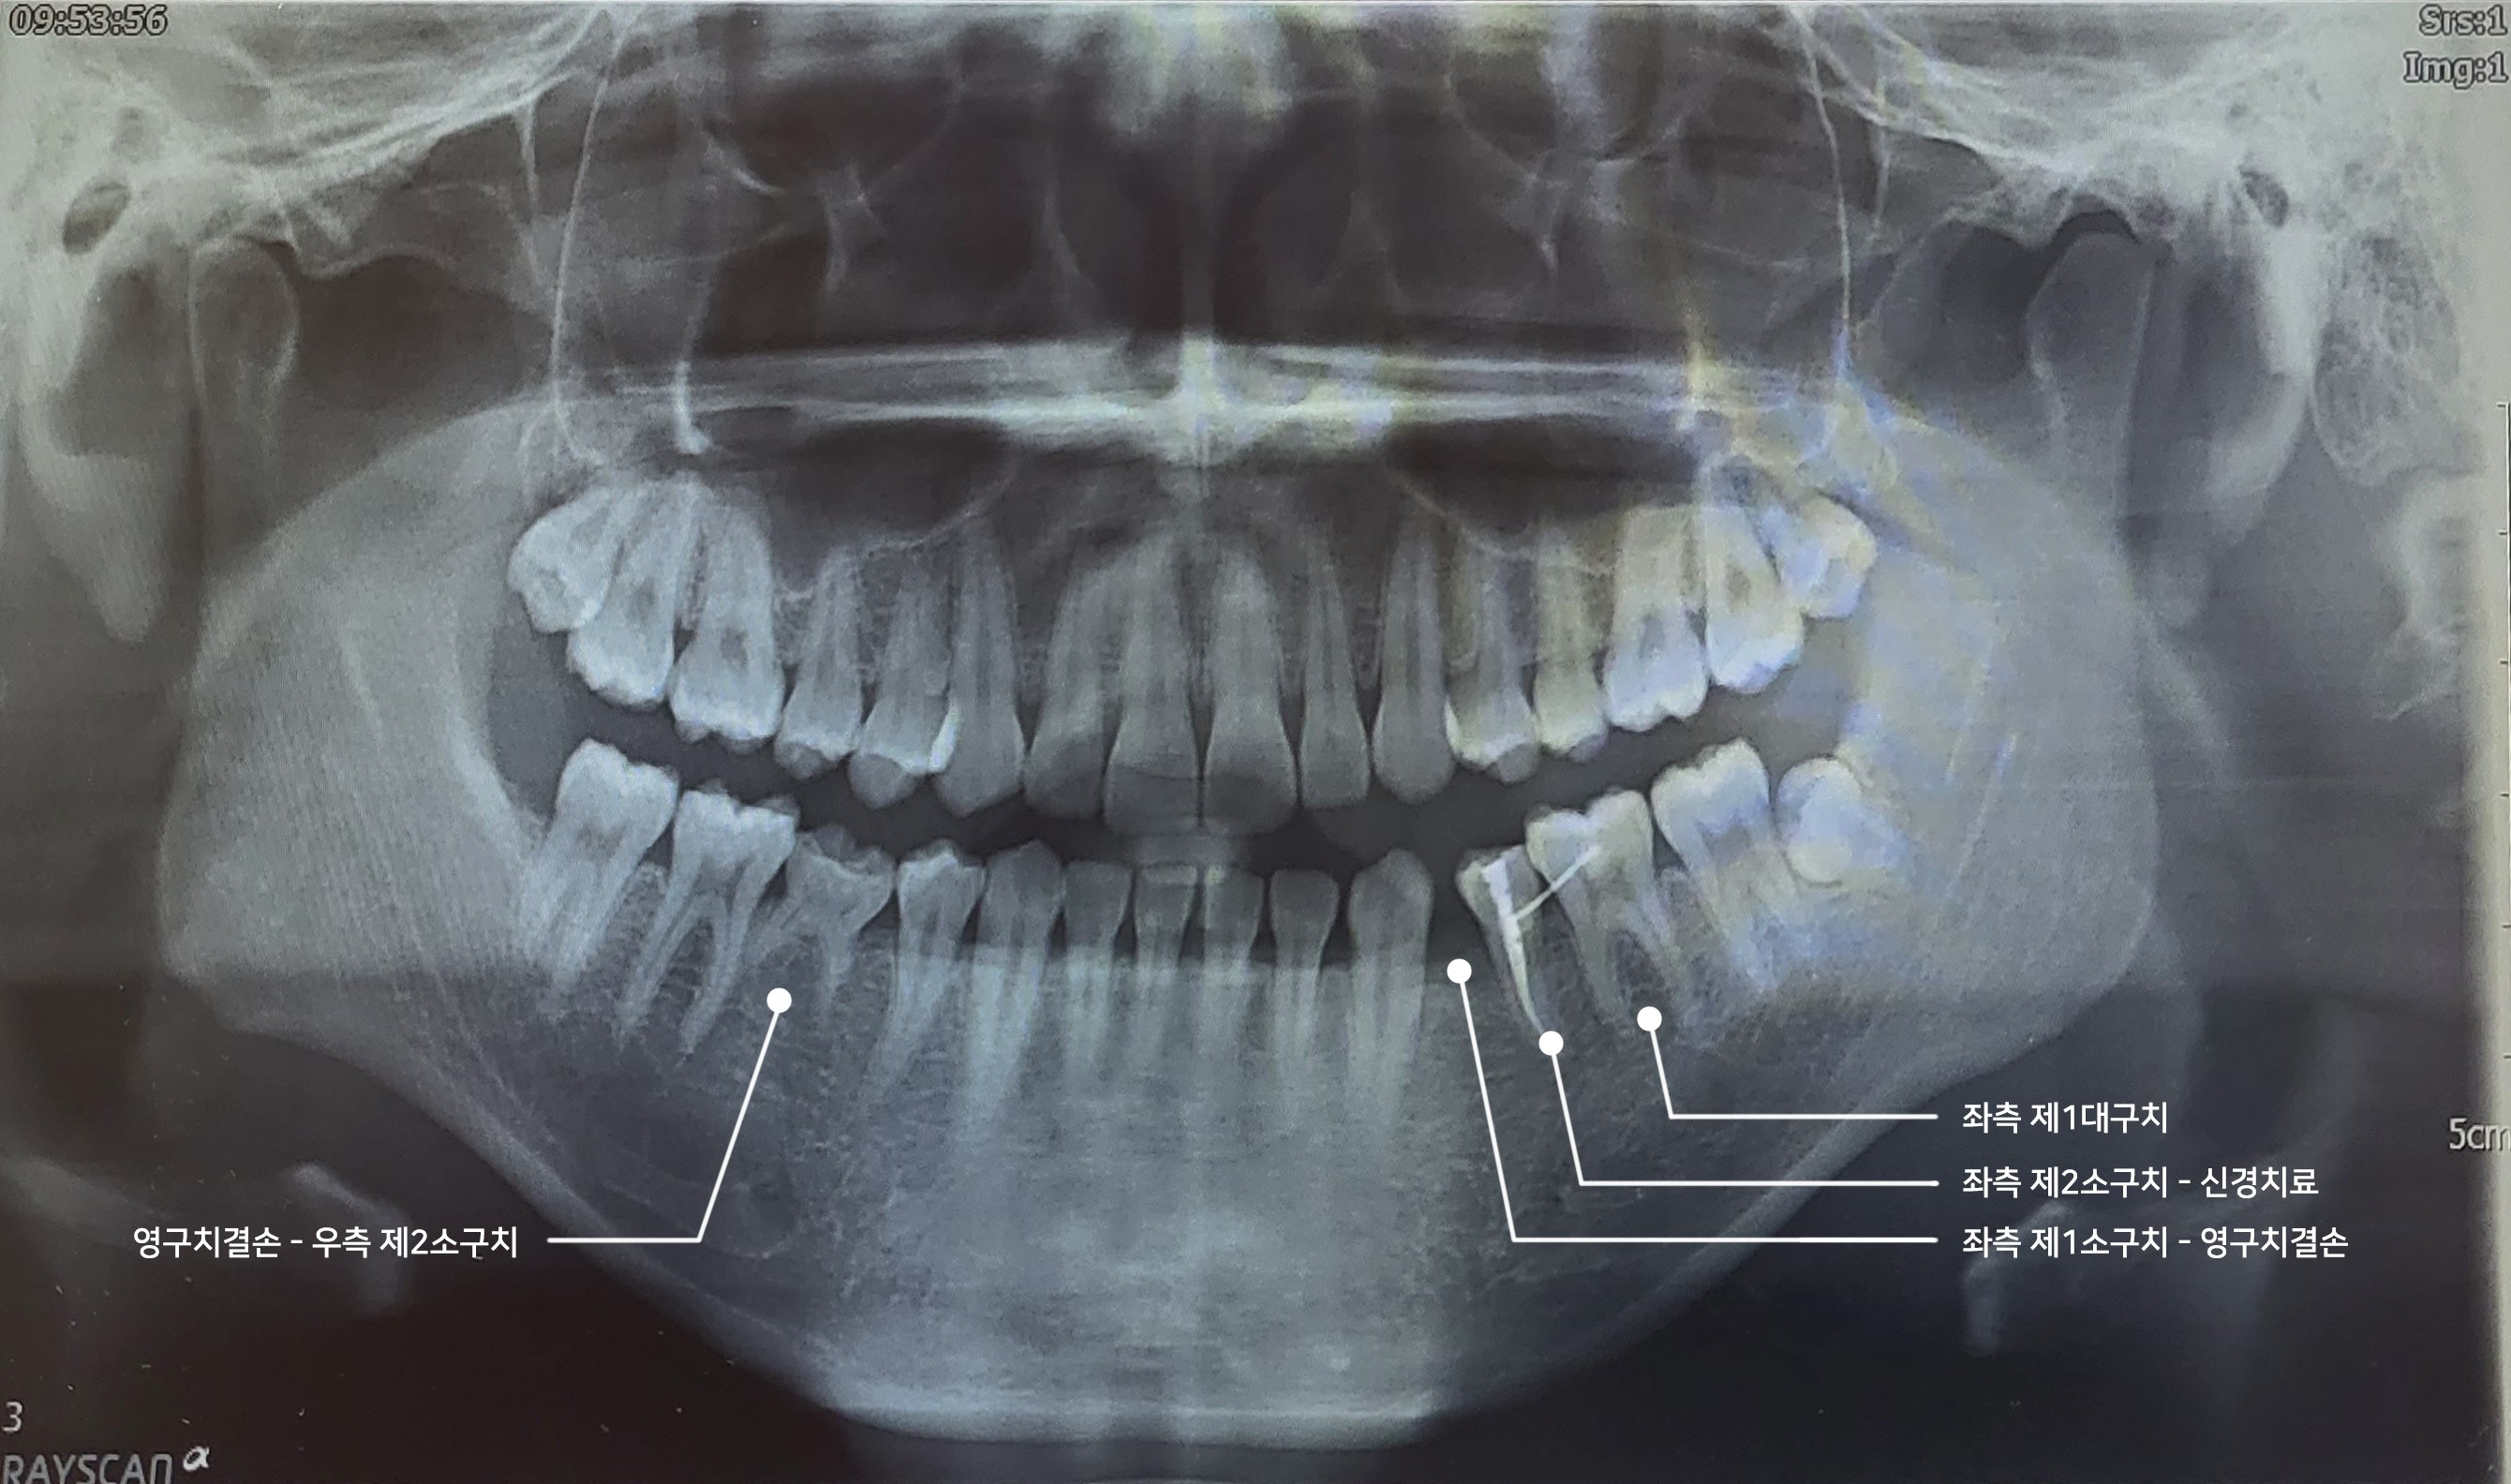

본인은 선천적으로 하악(아래턱)의 어금니 2개가 영구치가 없다. 의학적으로 정확한 용어인지는 모르겠지만 본인 기준의 하악 좌측 작은 어금니(제1소구치)와 하악 우측의 어금니(제2소구치)가 영구치가 없다. 오른쪽 턱의 제2소구치 유치는 튼튼하게 자리 잡고 있지만 왼쪽 제1소구치는 빠져버린 상태다.

2번째 치과에서는 임시로 씌워놨던 레진을 제거하고 나서는 아랫니가 빠진 빈자리에 예전처럼 탈착식 공간 유지장치를 하지 않았다. 그 대신 옆 어금니 2개에 와이어를 부착해 치아가 쓰러지지 않도록 했다. 다시 말해 왼쪽 제2소구치와 제1대구치에 와이어를 부착했다. 추가적으로 무너졌다가 다시 일으키느라 뿌리가 드러나고 아팠던 옆의 이(왼쪽 제2소구치)는 신경치료를 하게 되었다. 사실 이 당시에는 내가 받았던 시술이 신경치료인지 전혀 알지도 못하는 상태에서 받았다...^^;